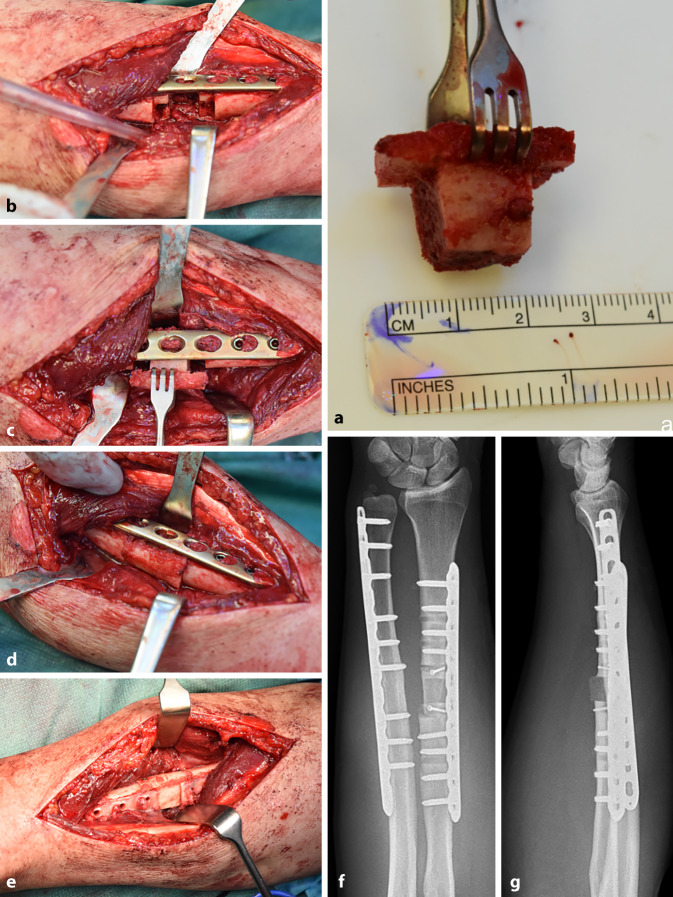

The management of shaft fractures of the upper extremities is an integral part of trauma surgery in the clinical routine. While sport-associated injuries predominate in young adults, the incidence of osteoporotic fractures greatly increases in older patients. Despite established treatment strategies, complications such as wound healing disorders, infections, neurovascular injuries, malalignment, pseudarthrosis and implant failure are frequent. An effective complication management requires detailed knowledge of the morphological features of fractures, individual risk factors and differentiated revision strategies. With the presentation of two clinical cases, we aim to highlight the necessity of individualized treatment concepts. Due to the increasing number of war casualties transferred for secondary treatment to Central Europe, the likelihood of encountering unfamiliar injury patterns, such as blast or gunshot wounds, is rising. This development presents new challenges in daily clinical practice. Physiotherapeutic and occupational therapy support play a central role in achieving favorable functional outcomes following revision surgery for diaphyseal fractures of the upper extremities. In geriatric care, orthogeriatric concepts have significantly decreased mortality and improved mobilization as well as self-sufficiency among older patients. Managing patient expectations and providing close supervision throughout the rehabilitation process are decisive factors for successful recovery.

Abstract Image